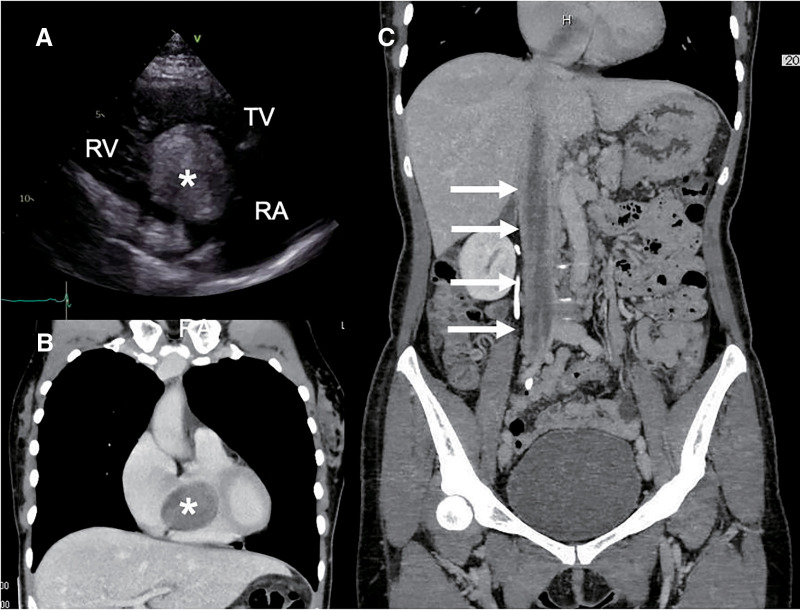

摘要静脉内平滑肌瘤病是一种罕见的良性肿瘤,起源于子宫平滑肌。一位50岁的女性在子宫切除术后3年出现心脏肿块。影像显示肿瘤从右髂内静脉延伸至右心房。通过两个阶段的手术实现了完全切除。第一阶段,行胸骨正中切口和腹膜后入路,在深低温循环停搏联合体外循环下切除心内肿瘤。术后给予促性腺激素释放激素(GnRH)激动剂治疗,第二阶段切除盆腔残余肿瘤和右侧卵巢。患者15个月无复发。

Intravenous leiomyomatosis with intracardiac extension is a rare benign tumor originating from uterine smooth muscle. A 50-year-old woman presented with a cardiac mass 3 years after hysterectomy. Imaging revealed a tumor extending from the right internal iliac vein to the right atrium. Complete resection was achieved via a 2-stage surgery. In the 1st stage, median sternotomy and a retroperitoneal approach were performed, and the intracardiac tumor was excised under deep hypothermic circulatory arrest with cardiopulmonary bypass. Postoperatively, gonadotropin-releasing hormone (GnRH) agonist therapy was administered, followed by a 2nd-stage resection of the residual pelvic tumor and right ovary. The patient remained recurrence-free for 15 months.